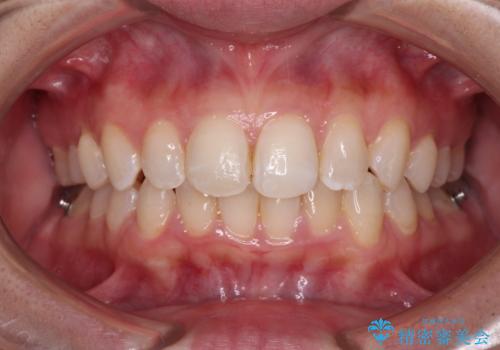

- 前歯のデコボコと歯肉に埋もれている奥歯を気にして来院された患者様です。

インビザラインでの治療を希望されていましたが、左右の下顎大臼歯が歯肉に埋もれており、特に右側は歯軸が顕著に傾斜していたため、インビザライン単独での治療は困難と判断し、ワイヤー装置を併用することとしました。

ワイヤー装置での下顎臼歯改善には時間がかかることが予想されたため、下顎のワイヤー矯正と並行して上顎をインビザラインで整え、その後インビザラインにより上下歯列を整える矯正治療を行うこととしました。

ワイヤー装置を併用したことで、レントゲン写真からも分かるとおり歯軸をしっかりと改善させることができました。